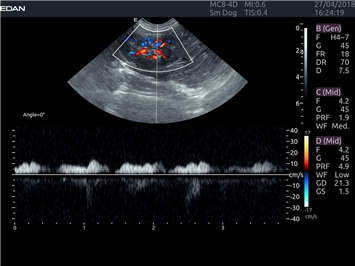

EDAN Acclarix LX4 VET представляет собой профессиональную ультразвуковую систему, специально разработанную для ветеринарных исследований. Сочетание стабильности, высокой производительности и эффективности делает эту систему идеальным выбором для современной ветеринарной практики.

Инновационные технологии обработки изображений:

• Адаптивная визуализация тканей:

• Оптимизация изображения для различных видов животных

• Улучшенная детализация структур

• Мультилучевое сложно-составное сканирование (SCI):

• Повышенная четкость изображения

• Улучшенная визуализация сложных анатомических структур

• Технология подавления зернистости:

• Снижение шумов изображения

• Повышение диагностической ценности